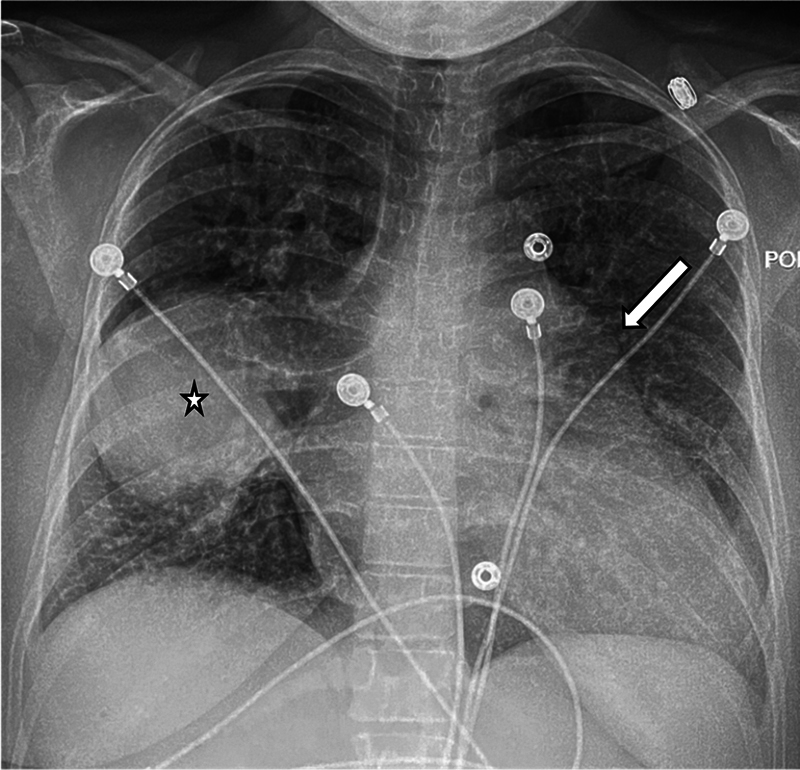

Ectopic origin of the right pulmonary artery (RPA) from the aorta is a rare congenital anomaly typically found in infants. We report an adult female presenting with shortness of breath diagnosed incidentally with ectopic RPA via computed tomography angiography. This case underscores the need to consider rare congenital anomalies in adults presenting with unexplained pulmonary symptoms.